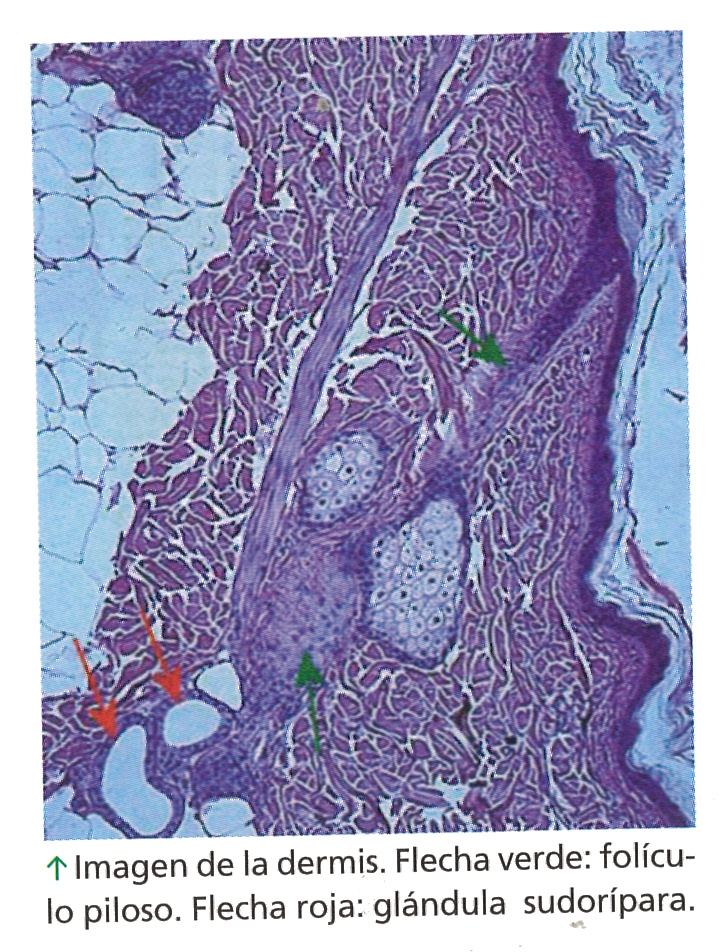

* Glandulas sudoríparas: liberan el sudor y ayuda a regular la temperatura del cuerpo.